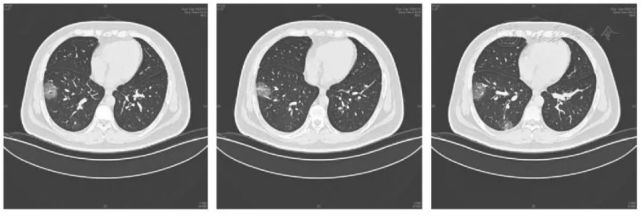

新冠肺炎患者肺部ct显示磨玻璃影(图片来自网络)

新冠肺炎的肺CT图片

新冠肺炎肺部影像